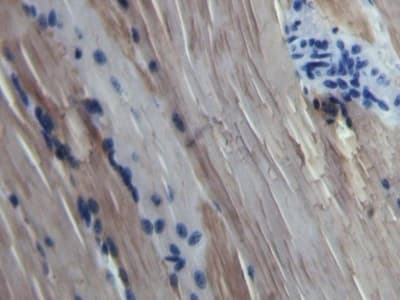

Rabbit Polyclonal Myoglobin antibody. Suitable for WB, IHC-P and reacts with Cow samples. Cited in 1 publication. Immunogen corresponding to Recombinant Full Length Protein corresponding to Cow Myoglobin.

Applications IHC-P, WB

Species Reactivity Cow